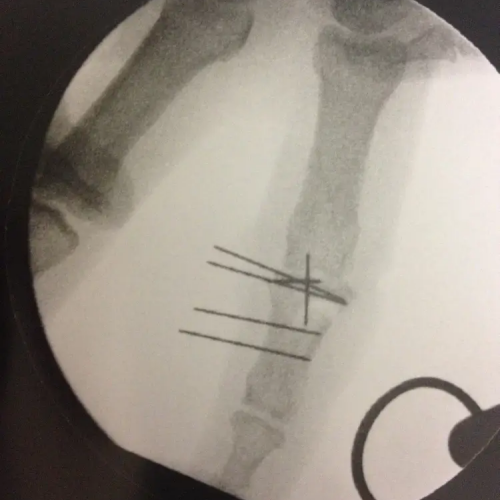

Dans le cadre des urgences de la main et du poignet, le chirurgien de la main Aude Le Corre est appelée pour la réalisation de soins ou pour des opérations chirurgicales pour des plaies, des infections, des brûlures, et de la traumatologie (fractures). Elle intervient aux urgences de la main depuis 2013.

Vous trouverez ci-dessous des exemples d'interventions SOS main :

- fractures